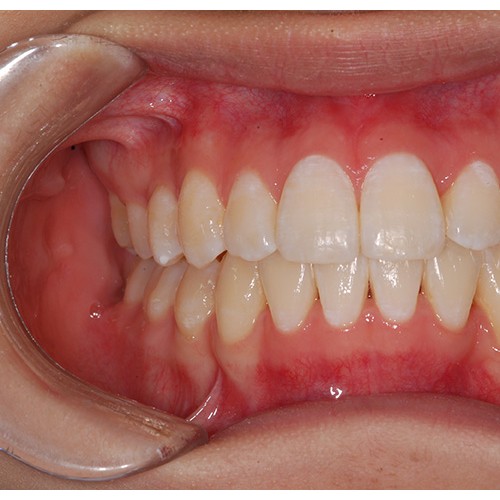

CHUNCHU'S ORTHODONTIC CLINIC# BEFORE_AFTER

춘추치과교정과를 방문해주신 분들의전후 사진을 확인해보세요.